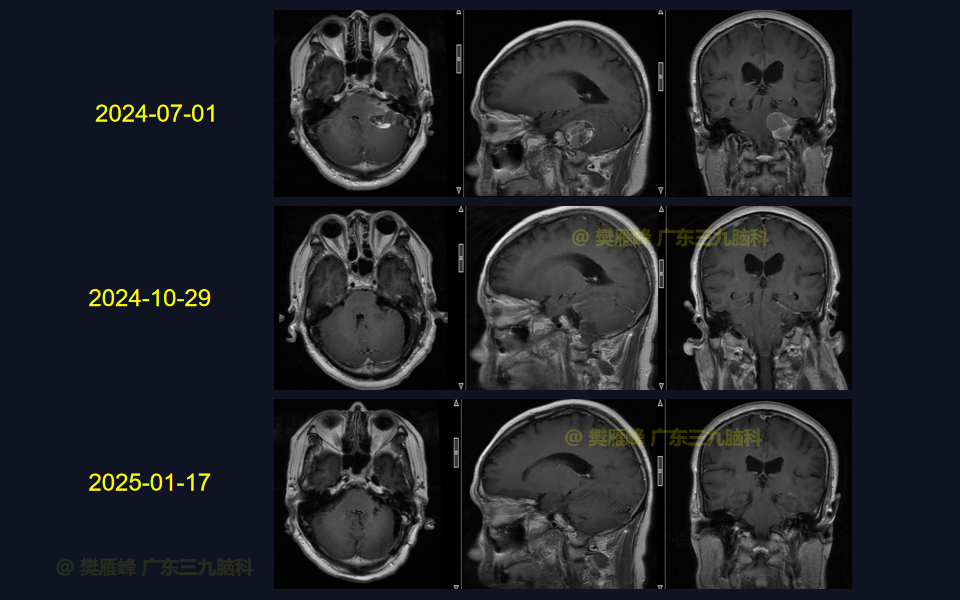

手术系列022:乙状窦后入路切除4级囊实性听神经瘤